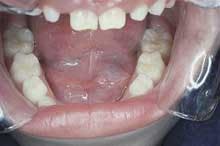

Intraoral examination revealed a well-defined, bluish dome-shaped swelling on the floor of the mouth (see photo). The lesion measured approximately 25mm in diameter and did not cross the midline. Palpation revealed a soft, fluctuant mass. No other soft tissue abnormalities were noted.

The ranula may be seen in patients of any age group. The typical presentation is that of a unilateral, dome-shaped swelling on the floor of the mouth. The surface of the lesion is smooth, and the color may vary from pinkish-red to a translucent blue. The lesions that are located close to the surface epithelium are more likely to appear bluish.

The ranula grows slowly and is painless. The size may vary from small to very large; the large lesions may result in displacement of the tongue. Upon palpation, the ranula feels compressible, soft, and fluctuant. A ranula may have a history of rupture and collapse followed by recurrence.